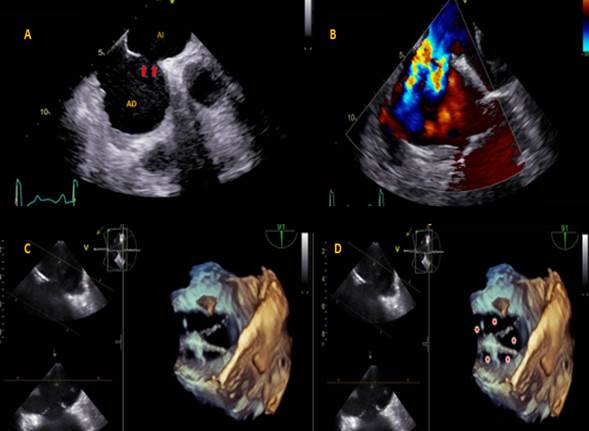

Presentamos un caso de paciente masculino de 61 años de edad, quien tenía como único antecedente extabaquismo y se encontraba en estudios preoperatorios para realización de herniorrafia umbilical. Sin embargo, al examen físico se evidenció soplo sistólico para esternal izquierdo medio, por lo que se le indicaron toma de estudios de extensión, entre ellos radiografía de tórax con silueta cardíaca aumentada de tamaño en cavidades derechas con signos indirectos de hipertensión pulmonar. Un ecocardiograma transtorácico evidenció hallazgos de dilatación de cavidades derechas y aneurisma del septum interauricular con posible defecto tipo CIA ostium secundum, por lo que se realizó ecocardiograma transesofágico (figura 1). Este mostró una comunicación interauricular multiperforada con flujo de izquierda a derecha, con septum interauricular y se observaron 6 orificios separados por delgados remanentes septales.

Figura 1 A-B: ecocardiograma transesofágico que demuestra un gran defecto interauricular con presencia de múltiples jets de color, lo que sugiere múltiples perforaciones a este nivel. C-D: reconstrucción 3D del defecto interatrial que confirma y demuestra una comunicación multiperforada como imagen de alto impacto académico.